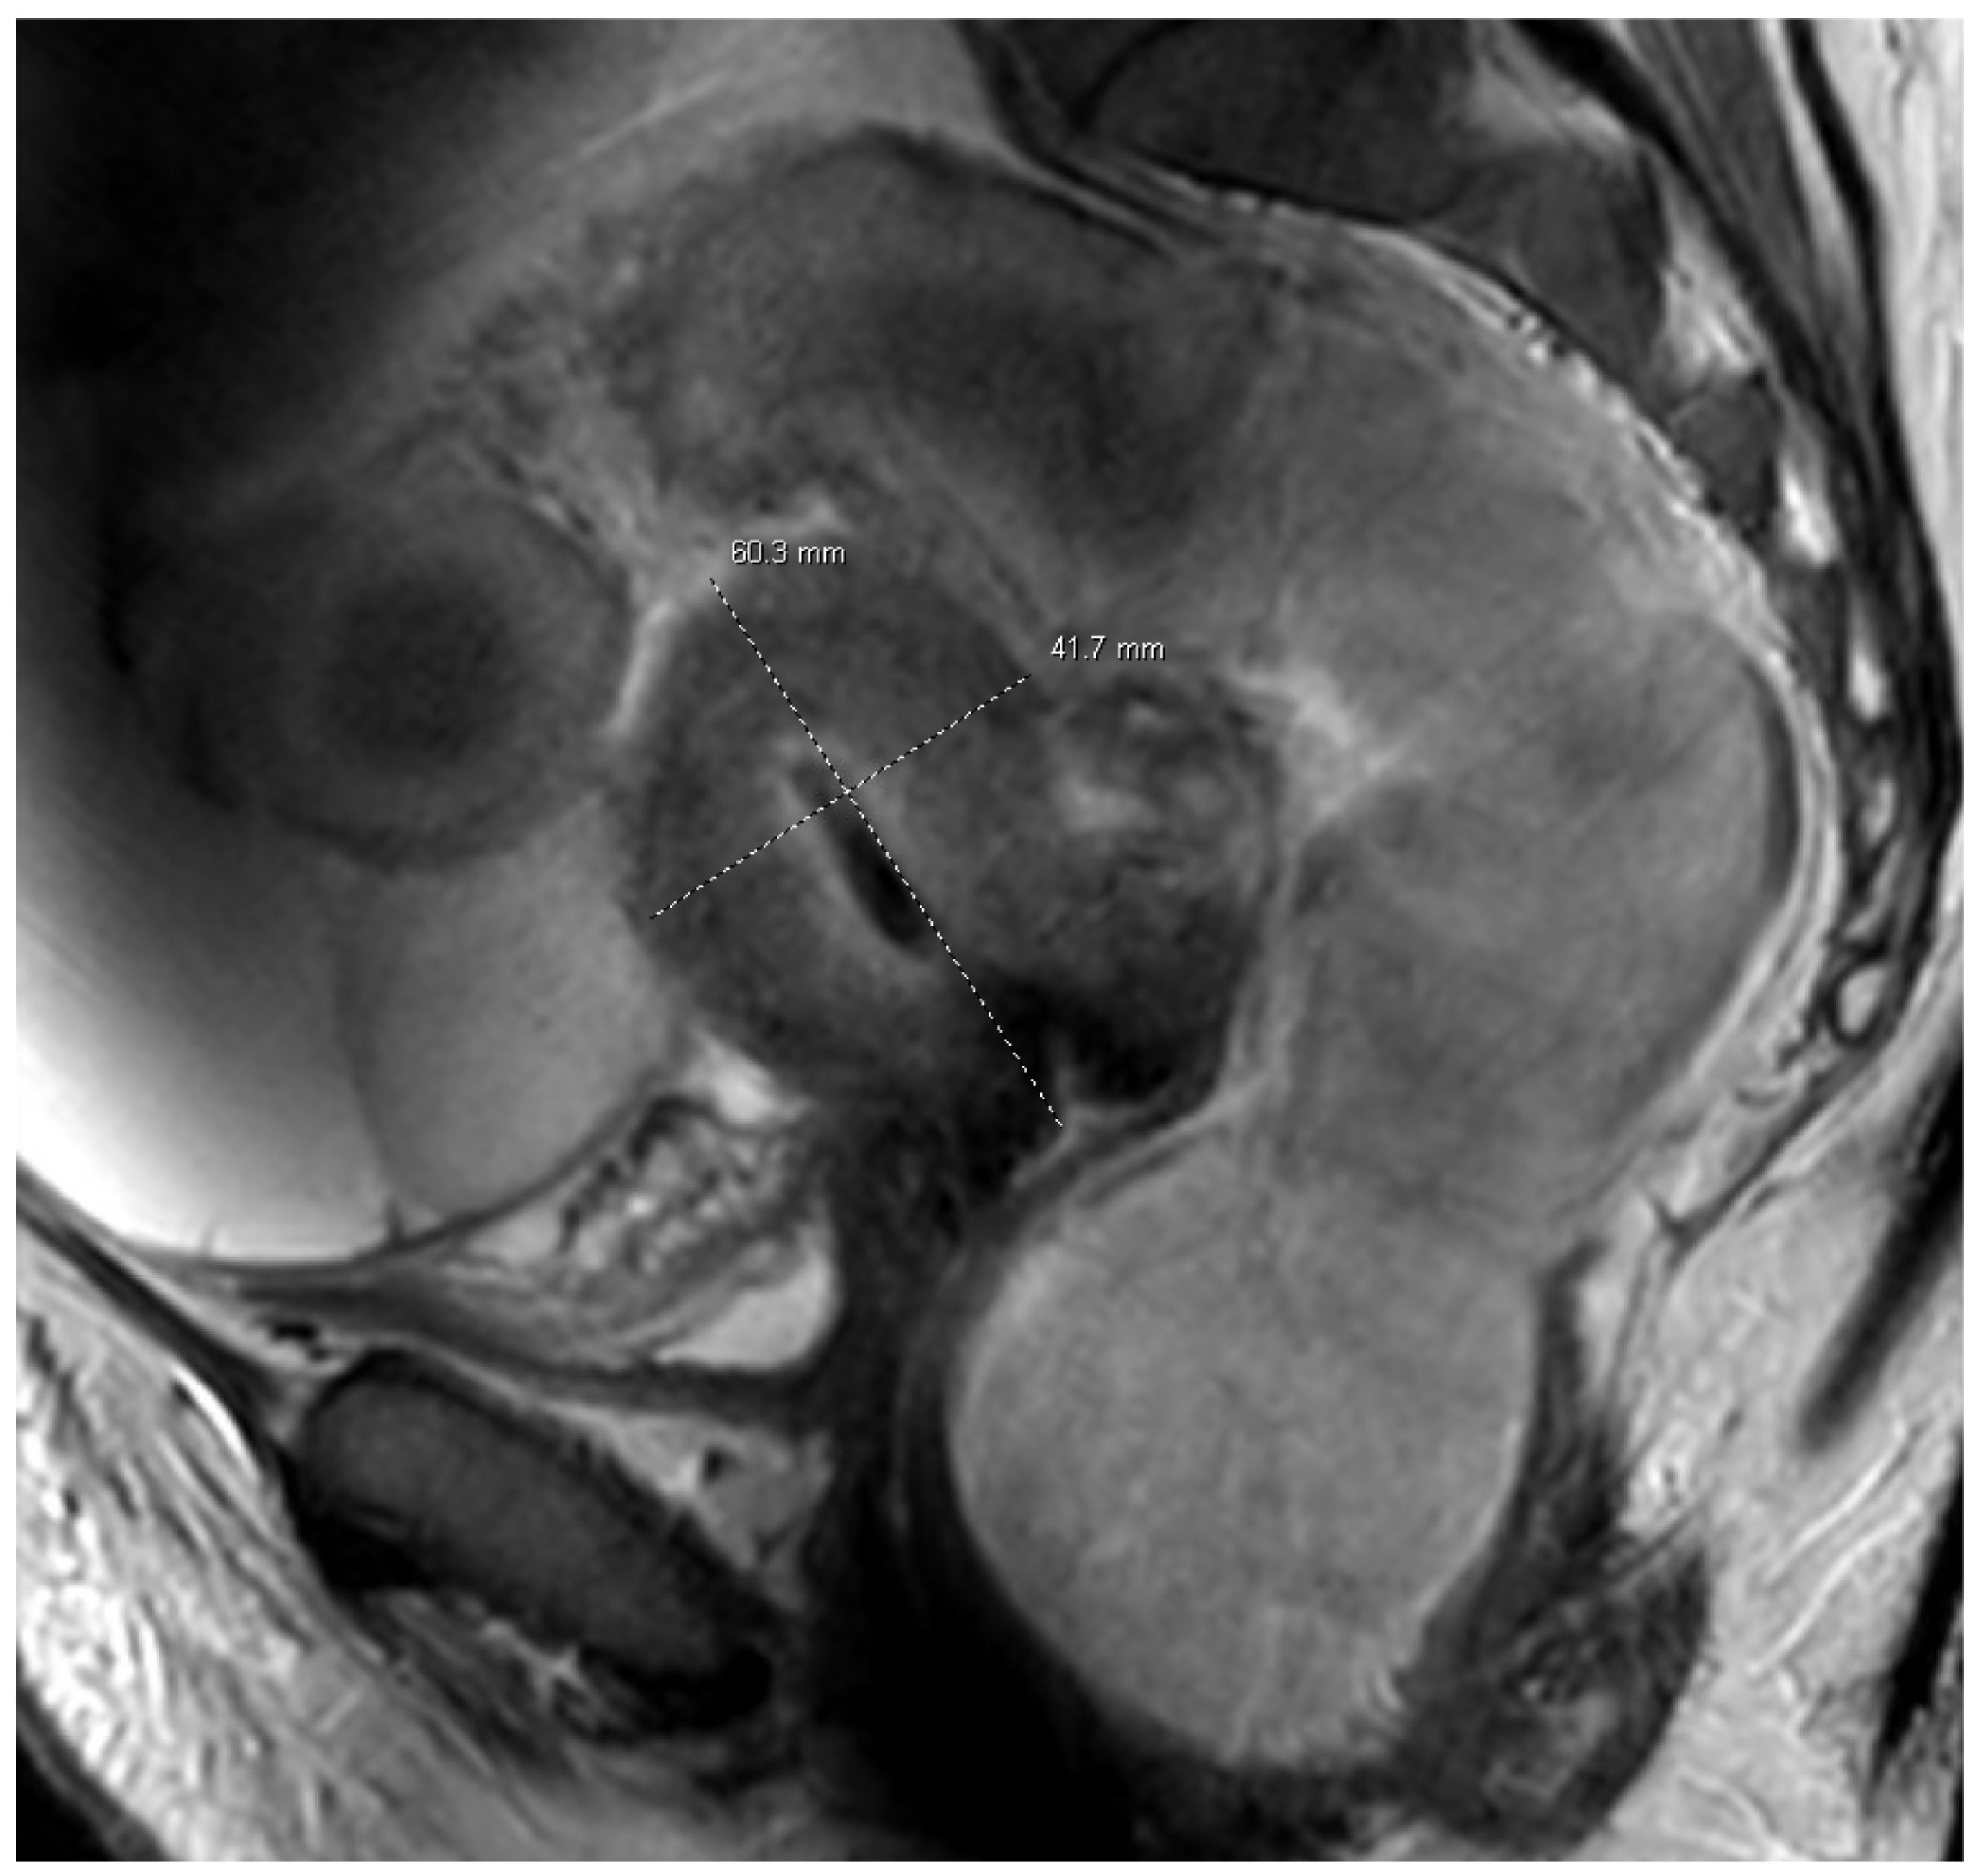

2. Case Presentation